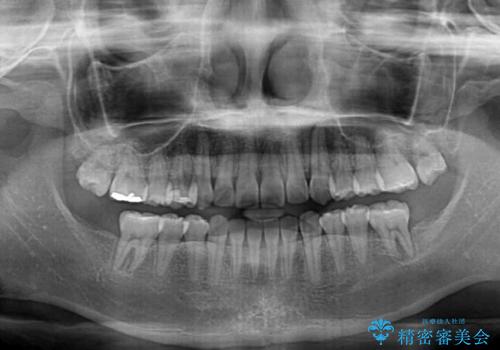

順調に後方移動することができ、わずか1年強で治療を終えることができました。

顎骨が小さいので第二大臼歯が欠損しても負担は少ないと思いますが、奥歯でもっとしっかりと咬みたいということであれば、インプラント補綴治療を4本分行うこととなります。